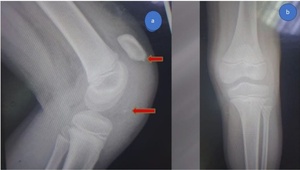

At the emergency room, radiographs were performed, which revealed a high-riding patella with a noticeable joint effusion as well as a small osteochondral fragment positioned distally to the patella. (Figure 2) As a result of the high-riding patella on the radiographs and the avulsion of the distal osteochondral side of the patella, a patellar sleeve fracture was detected. The surgery was scheduled for the next day.